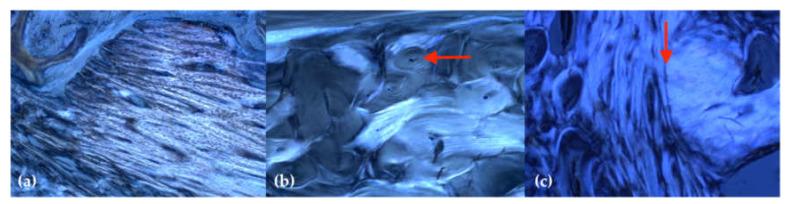

The aim of this randomized, controlled animal exploratory trial was to investigate the influence of local application of aminobisphosphonate pamidronate during the socket preservation procedure. Mandibular premolars were extracted in five Göttingen minipigs. Two animals underwent socket preservation using BEGO OSS (n = 8 sockets) and three animals using BEGO OSS + Pamifos (15 mg) (n = 12 sockets). After jaw impression, cast models (baseline, eight weeks postoperative) were digitized using an inLab X5 scanner (Dentsply Sirona) and the generated STL data were superimposed and analyzed with GOM Inspect 2018 (GOM, Braunschweig). After 16 weeks, the lower jaws were prepared and examined using standard histological methods. In the test group (BEGO OSS + pamidronate), buccooral dimensional loss was significantly lower, both vestibulary (0.80 ± 0.57 mm vs. 1.92 ± 0.63 mm; = 0.00298) and lingually (1.36 ± 0.58 mm vs. 2.56 ± 0.65 mm; = 0.00104) compared with the control group (BEGO OSS). The test group showed a significant difference between vestibular and lingual dimensional loss ( = 0.04036). Histology showed cortical and cancellous bone in the alveolar sockets without signs of local inflammation. Adjuvant application of pamidronate during socket preservation reduces alveolar dimensional loss significantly. Further investigations with regard to dose-response relationships, volume effects, side effects, and a verification of the suitability in combination with other bone substitute materials (BSMs) are necessary.

本随机对照动物探索性试验旨在研究局部应用氨甲膦酸盐帕米膦酸盐在牙槽窝保存过程中的影响。在五只哥廷根小型猪中拔除下颌前磨牙。两只动物使用 BEGO OSS(n = 8 个牙槽窝)进行牙槽窝保存,三只动物使用 BEGO OSS + Pamifos(15 mg)(n = 12 个牙槽窝)。下颌印象后,使用 inLab X5 扫描仪(登士柏西诺德)对铸模模型(基线,术后 8 周)进行数字化,并使用 GOM Inspect 2018(GOM,不伦瑞克)对生成的 STL 数据进行叠加和分析。16 周后,准备下颌并使用标准组织学方法进行检查。在实验组(BEGO OSS + 帕米膦酸盐)中,颊侧/牙槽嵴宽度损失明显低于对照组(BEGO OSS),颊侧(0.80 ± 0.57 mm 比 1.92 ± 0.63 mm; = 0.00298)和舌侧(1.36 ± 0.58 mm 比 2.56 ± 0.65 mm; = 0.00104)。实验组颊侧和舌侧宽度损失有显著差异( = 0.04036)。组织学显示牙槽窝内皮质骨和松质骨,无局部炎症迹象。在牙槽窝保存过程中辅助应用帕米膦酸盐可显著减少牙槽嵴宽度损失。需要进一步研究剂量反应关系、体积效应、副作用,并验证其与其他骨替代材料(BSMs)联合使用的适用性。